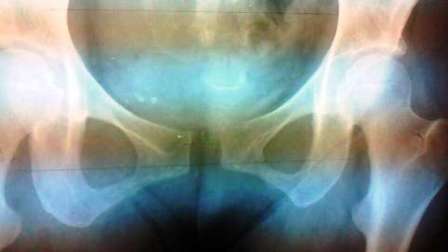

骨盤は、歪み(ゆがみ)ますよ。まずは、実際に妊娠中に骨盤の下側が広がったときのレントゲンです↓

https://sujikotu-seitai.com/tikotuketugourikai-2/

実際に歪んだ(ゆがんだ)骨盤のレントゲン写真は、こちらです↓

http://blogs.yahoo.co.jp/yamada_akira1951/23868819.html

これくらい歪む(ゆがむ)方は少ないですが、少しだけ歪んで(ゆがんで)いらっしゃる方は実際に、たくさんいらっしゃいます。